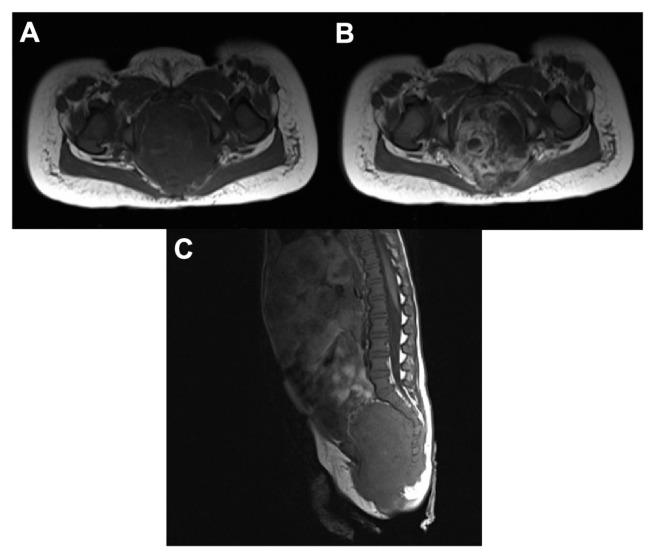

Gadobutrol is a 1-molar gadolinium-based contrast agent with well-characterized safety and efficacy for magnetic resonance imaging (MRI) in adults and children ≥ 2 years old. This observational study assessed gadobutrol-enhanced MRI in children < 2 years of age. Sixty infants (mean age 11.1 months) underwent MRI using gadobutrol at standard dose of 0.1 mL/kg (0.1 mmol/kg) body weight. MRI examinations included brain, spine, and neck (n = 24), subcutaneous soft tissues (n = 14), chest, abdomen, and pelvis (n = 12), musculoskeletal system (n = 7) and vascular system (n = 3). No patients experienced adverse events related to gadobutrol injection. In 57 patients with confirmed diagnoses, gadobutrol-enhanced MRI provided findings consistent with confirmed pathologies. This study indicates that gadobutrol at a standard dose for MRI is safe in patients aged < 2 years and provides diagnostic information for multiple pathologies.